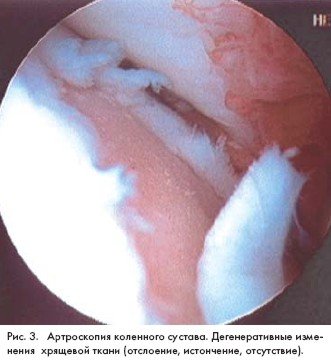

Характерные изменения при артроскопии коленного сустава

С помощью диагностической термографии подтверждаются характерные для артрита локальные изменения теплообмена. УЗИ суставов помогают определить наличие выпота в его полости, а также параартикулярных изменений. Данные радионуклидной сцинтиграфии позволяют судить о реакции костной ткани и активности воспаления. По показаниям проводится диагностическая артроскопия. Для определения степени функциональных нарушений в суставах при артрите используются методики измерения амплитуды пассивных и активных движений, подография (регистрация продолжительности отдельных фаз шага).